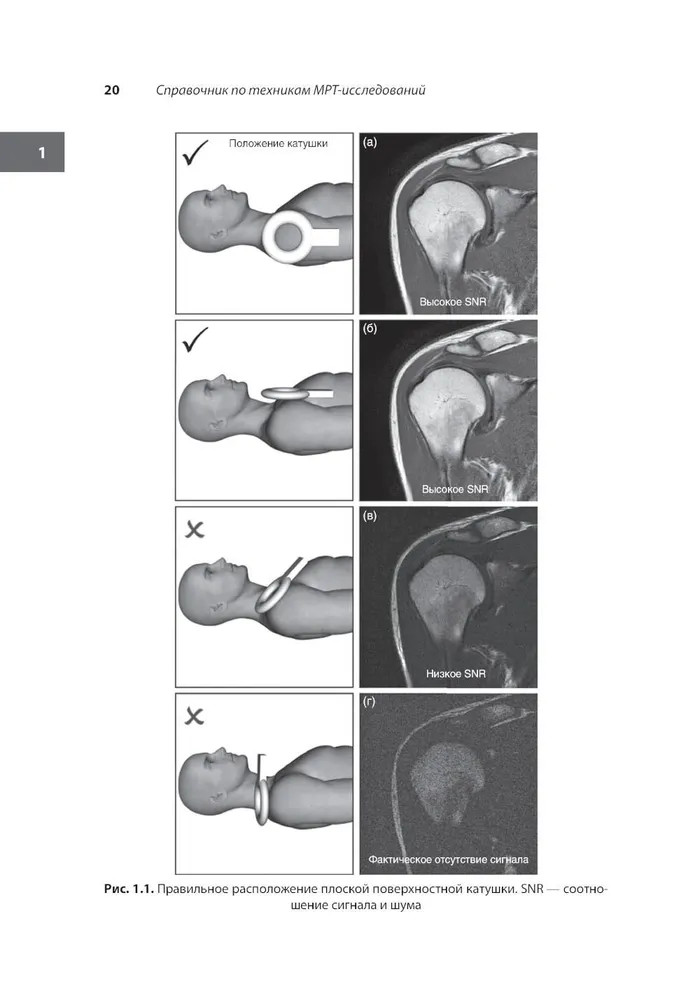

💳 Оплатить за товар можно при получении 🇰🇿 Есть бесплатная доставка по Казахстану 🎁 Копите бонусы с каждой покупки Книга представляет собой руководство по работе с магнитно-резонансными сканерами и предназначена в первую очередь для повышения квалификации пользователей этих систем. Приведены общие теоретические аспекты МРТ-диагностики и даны практические советы, касающиеся различных аспектов используемого оборудования, безопасности и подготовки пациентов, и используемых в ходе исследований контрастных препаратов. Описаны наиболее часто применяемые техники МРТ-диагностики, рассмотрены показания, положение пациента, оснащение, рекомендуемые протоколы сканирования, наиболее распространенные артефакты и советы по оптимизации качества изображений. Также представлены техническое руководство и рекомендации по использованию контрастных средств. На многочисленных схемах и изображениях показаны плоскости сканирования, даны рекомендации по выполнению срезов и используемым импульсным последовательностям, что как раз отражает в первую очередь техническую направленность данного руководства. |